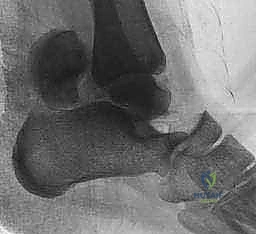

2. التصوير الإشعاعي (الأشعة السينية - X-rays)

هي الخطوة الأولى. تُطلب صور من زوايا متعددة:

* الرؤية الأمامية الخلفية (AP).

* الرؤية الجانبية (Lateral).

* رؤية الهاون (Mortise view).

* رؤية كانال (Canale View): وهي وضعية تصوير خاصة جداً لتقييم عنق الكاحل وتحديد درجة الإزاحة بدقة.

3. التصوير المقطعي المحوسب (CT Scan) - المعيار الذهبي

في عيادة الأستاذ الدكتور محمد هطيف، يُعتبر التصوير المقطعي المحوسب ثلاثي الأبعاد (3D CT Scan) إجراءً روتينياً وحتمياً لأي كسر في عظم الكاحل. توفر الأشعة المقطعية تفاصيل دقيقة للغاية عن خطوط الكسر، مدى التفتت (Comminution)، وحجم الإزاحة المفصلية التي لا يمكن رؤيتها بالأشعة السينية العادية. بناءً على هذه الصور، يقوم الدكتور هطيف ببناء استراتيجية الجراحة (أين سيفتح، ما نوع الشرائح والمسامير التي سيستخدمها، وكيف سيعيد بناء العظم).